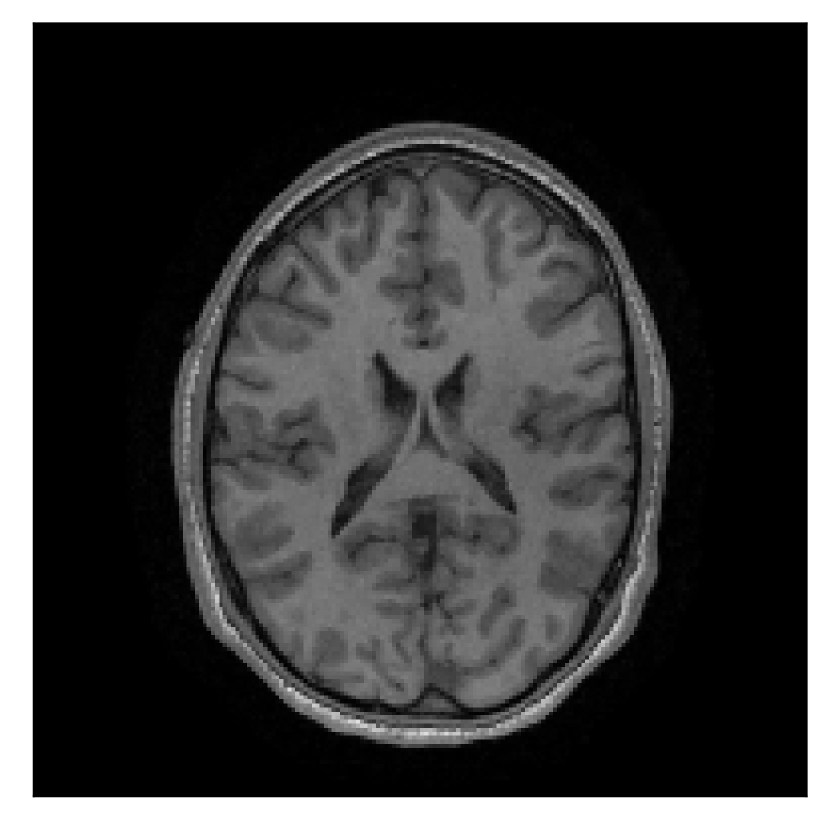

We consider three levels of motion corruption: (i) the volunteer moves once, (ii) the volunteer moves twice, and (iii) the volunteer moves five times. The volunteer is instructed to change its head position every time it is prompted to do so, and maintain that position in between instructions. We use T2-FLAIR-weighted contrasts as corrupted scans, with T1-weighted contrast as a reference (see Table 1 for further details). The corrupted acquisition employs randomized sampling.

4.1 Experiment 1: robustness test

We gather the results for the robustness test described in Section 3.1 (volunteer 1) in Figures 2, 4, and 6 for motion corruption mechanisms associated to one, two, and five changes of position, respectively. Furthermore, we juxtapose the corrected images with varying degrees of corruption in Figure 8. We observe that the proposed method consistently ameliorates the corrupted scan. The quality indexes based on PSNR and SSIM show only a modest decrease in correction quality as a function of motion complexity (Figure 8).

| Section 3.1, Figure 4 | Sagittal | 25.78 | 27.76 | 0.7263 | 0.7816 |

| Coronal | 28.19 | 29.73 | 0.7847 | 0.8244 | |

| Axial | 27.79 | 29.70 | 0.8104 | 0.8362 | |

| Section 3.1, Figure 4 | T2-FLAIR | Completely corrected | Some blurring | No additional artifacts | Good grey white matter differentiation |